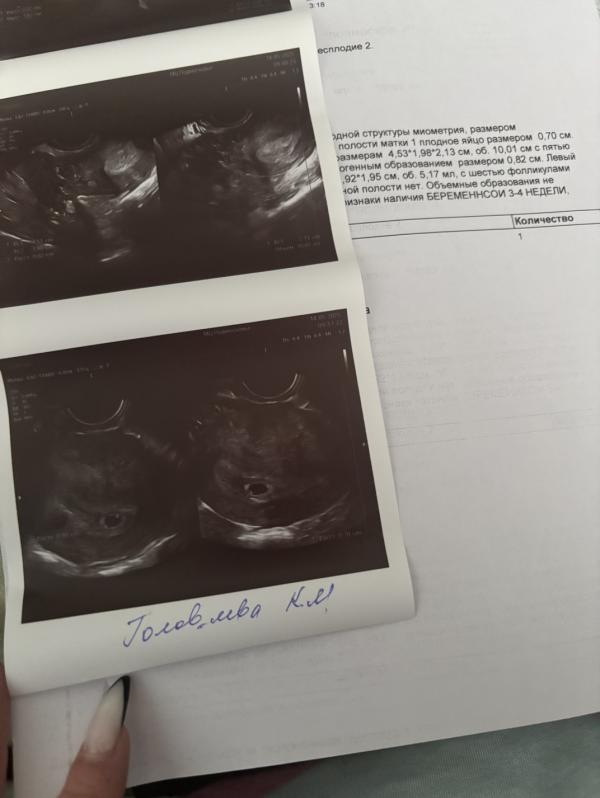

По месячным 5 недель 4 дня, плодное яйцо 0,70 см

Поставили беременность 3-4 недели, ну по таблицам в интернете, соответствует 5,3-5,4 недялям